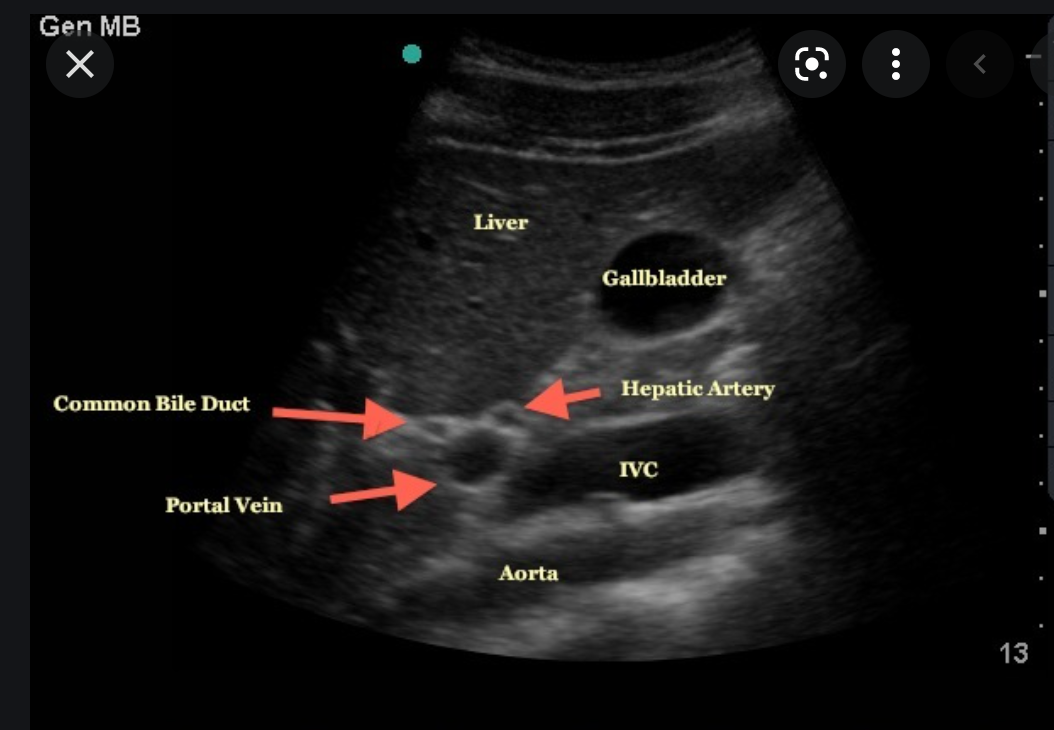

describe the location of the HA relative to the CBD

- Most common 80%

- HA is between the CBD and the PV

- HA medial to the main PV and

- CBD lateral to the PV

- Less common 20%

- HA anterior to CBD

- HA posterior to PV

where is the CHD measured on US?

What are the normal measurements?

- CHD measurements (inner wall to inner wall) are performed at the level of the hepatic artery

- Normal measurements

- <7mm in normal fasting patients <60yo

- <10 mm in normal fasting patients >60yo

- <11mm in pts with previous

- surgery

- CBD obstruction

- Fatty meal challenge

- if CHD enlarges more than 2mm after fatty meal, it indicates obstruciton